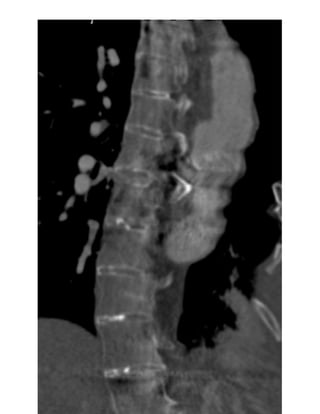

Fig. 16: Dural ectasia according to Ahn criteria. Reformated CT scan shows a sagital

width of the dural sac at level S1 greater than at level L4.

Page 10 of44 A less common cardiovascular manifestation of Marfan syndrome is dilatation of the main pulmonary artery. The upper values have been established at 24 mm at the pulmonary artery bifurcation and 34mm at the pulmonary artery root[23]. Fig. 15 on page 24 2- Dural ectasia Dural ectasia (DE) is one of the major criteria of Marfan syndrome in the Ghent nosology. It has a prevalence in Marfan syndrome of about 60% and its severity increases with aging[24]. It is a widening of the dural sac or spinal nerve root sleeves, usually associated with bony erosions of the posterior vertebral body, increased thinning of the cortex of the pedicles and laminae, widening of the neural foramina, or presence of a meningocele[25]. Ahn Criteria Ahn et al. described that dural ectasia is present if one major or two minor criteria are present. Major criteria: - width of the dural sac at a level below S1 greater than that above L4. Fig. 16 on page 25 - Presence of an anterior sacral meningocele. It is present when there is a herniation of the dural sac through a defect in the anterior surface of the sacrum or when the sacral meninges are herniating anteriorly into the pelvis through a widened foramen[26]. Fig. 17 on page 27 Minor criteria: -scalloping greater than 3.5 mm at the level of S1. Fig. 18 on page 27 - nerve root sleeve diameter greater than 6.5 mm at the level of L5[27]. Oosterhof criteria According to Oosterhof et al, dural sac ratio from levels L1 through S1 in adult patients have to be greater than respectively 0.64, 0.55, 0.47, 0.48, 0.48, and 0,57 in dural ectasia. A dural sac ratio is calculated for each level by dividing the sagittal dural sac diameter by the midsagittal vertebral body diameter [28]. Fig. 19 on page 29, Fig. 20 on page 31

Page 27 of44 Fig. 16: Dural ectasia according to Ahn criteria. Reformated CT scan shows a sagital width of the dural sac at level S1 greater than at level L4. Fig. 17: Anterior meningocele. Axial CT scan shows herniation of sacral meninges into the pelvis (arrow)and a bilateral dilatation of nerve root sleeves at level S1.